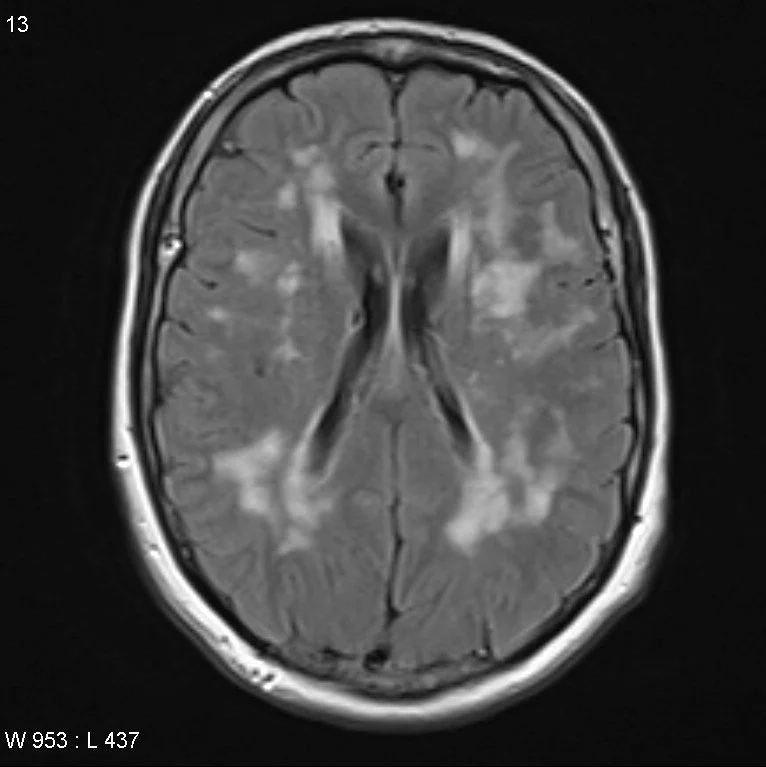

Cerebral Autosomal Dominant Arteriopathy with Subcortical Infarcts and Leukoencephalopathy (CADASIL)

• Autosomal dominant mutation in NOTCH 3 gene causing vasculopathy which results in recurrent ischemic infarcts and eventually vascular dementia

• This is basically early onset multi-infarct dementia

• Age 30-50 = TOO YOUNG FOR DEMENTIA AND RECURRENT STROKES

• Imaging

• Confluent white matter T2 hyperintensities

• Temporal lobe and external capsule are classic locations

• Occipital lobe and cortex are typically spared